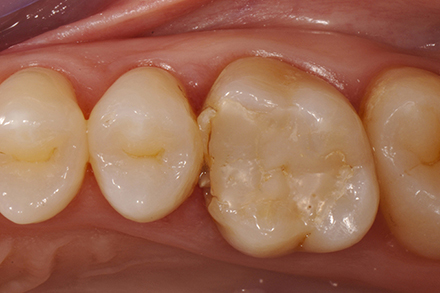

Initial situation: The patient was complaining about the lack of a contact point to the neighboring tooth. She was suffering occasional pain while chewing.